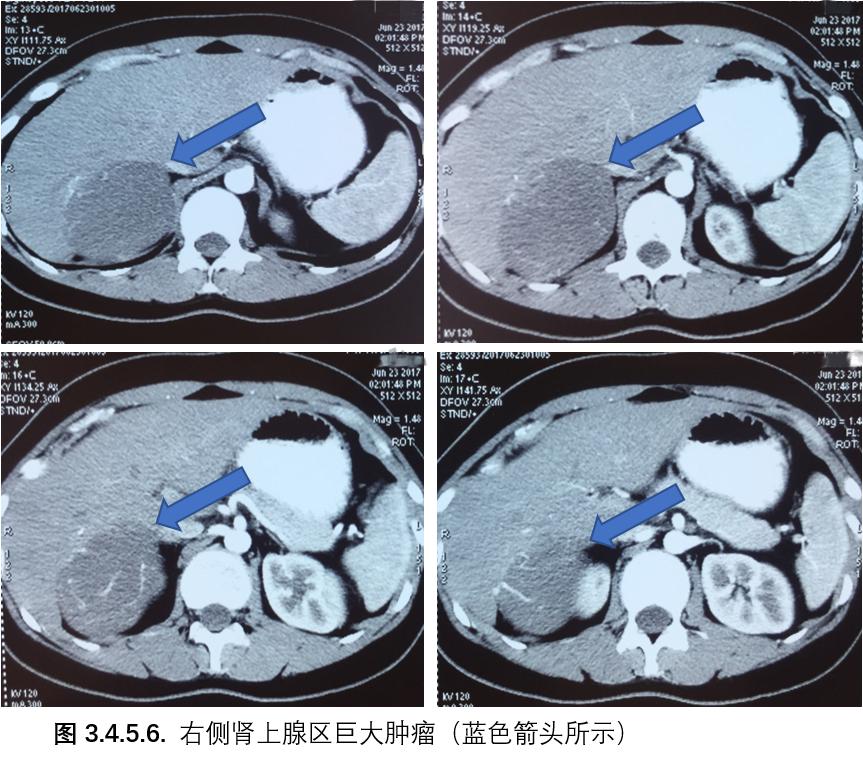

PET/CT检查: 右侧肾上腺区可见低密度团块影,呈不均匀放射性摄取增高,大小8.9cmx6.6cmx6.9cm,SUVmax6.2,考虑恶性病变可能。 (见图3,4,5,6)

放射科: 阅外院腹盆腔增强CT片,右侧肾上腺区等回声肿物,最大直径约8.8cm,动脉期强化明显,静脉期快速廓清,考虑肾上腺肿瘤,恶性可能。

核医学科: PET/CT提示右侧肾上腺区低密度肿瘤,呈不均匀放射性摄取增高,大小约8.9cmx6.6cmx6.9cm,SUVmax 6.2,考虑恶性病变可能性大。

泌尿外科: 患者17岁女性,有面部变圆等库欣综合征表现,有典型*疮痤**、声音低沉、多毛、月经减少等男性化表现,内分泌检查提示睾酮和硫酸脱氢表雄酮明显升高,高皮质醇血症和ACTH<5。腹部CT示右肾上腺区肿瘤约8cm。诊断方面:定位诊断为右侧肾上腺区肿瘤,定性诊断肾上腺皮质来源库欣肿瘤,皮质癌可能性大。治疗方面:患者肾上腺肿瘤较大,大小约8cm,根据指南推荐,建议行开放手术,术中细致操作,避免肿瘤破裂,应尽可能切净周围脂肪组织。